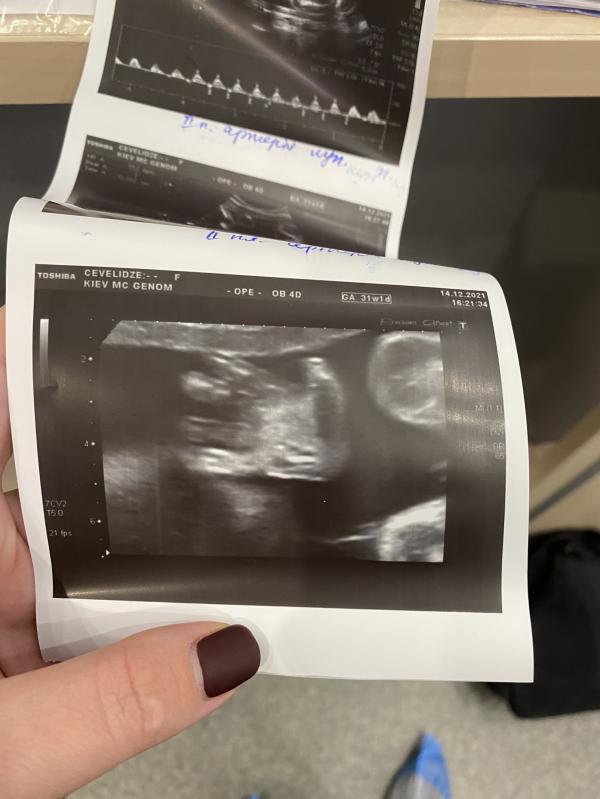

✅31 тиждень , 14 грудня 16.00 - і на узд я бачу погіршення показників кровотоку малого, плаценти і приймаю рішення їхати в пологовий.

P.S. фото моє, ручка нашого Ангела - Тимофійка на узд перед кесаревим розтином.